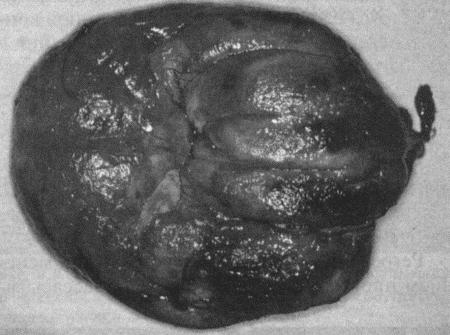

Фиг. 4.14.

Ткань, удаленная при резекции подслизистой при гиперплазии влагалища, изображенной на фиг. 4.12 (с любезного разрешения Dr Martin Sullivan)

Для лечения племенных животных рекомендуют резекцию подслизистой (фиг. 4.14). Операцию проводят в течение эструса, поэтому геморрагия может представлять серьезную опасность. По некоторым данным, патология имеет наследственный характер, в связи с чем хирургическое вмешательство представляется неэтичным.